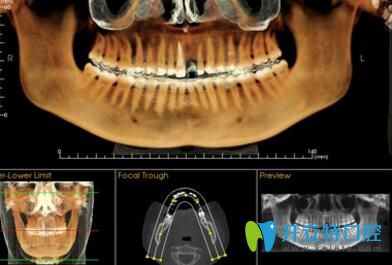

? 1、詳細測量數(shù)據(jù):

? 采用診療標準,在制定精細的矯正方案前,必須通過數(shù)字化診療,集全景,頭顱、CBCT功能于一體,能夠精準定位頭顱數(shù)據(jù)采集,提供高清晰度3D診斷圖片,采集口腔全景數(shù)據(jù),提高治療效果,因此牙齒將準確的向設計好的方向移動,呈現(xiàn)更美的口腔弧度。

長沙美萊口腔牙齒矯正優(yōu)勢詳細測量數(shù)據(jù)